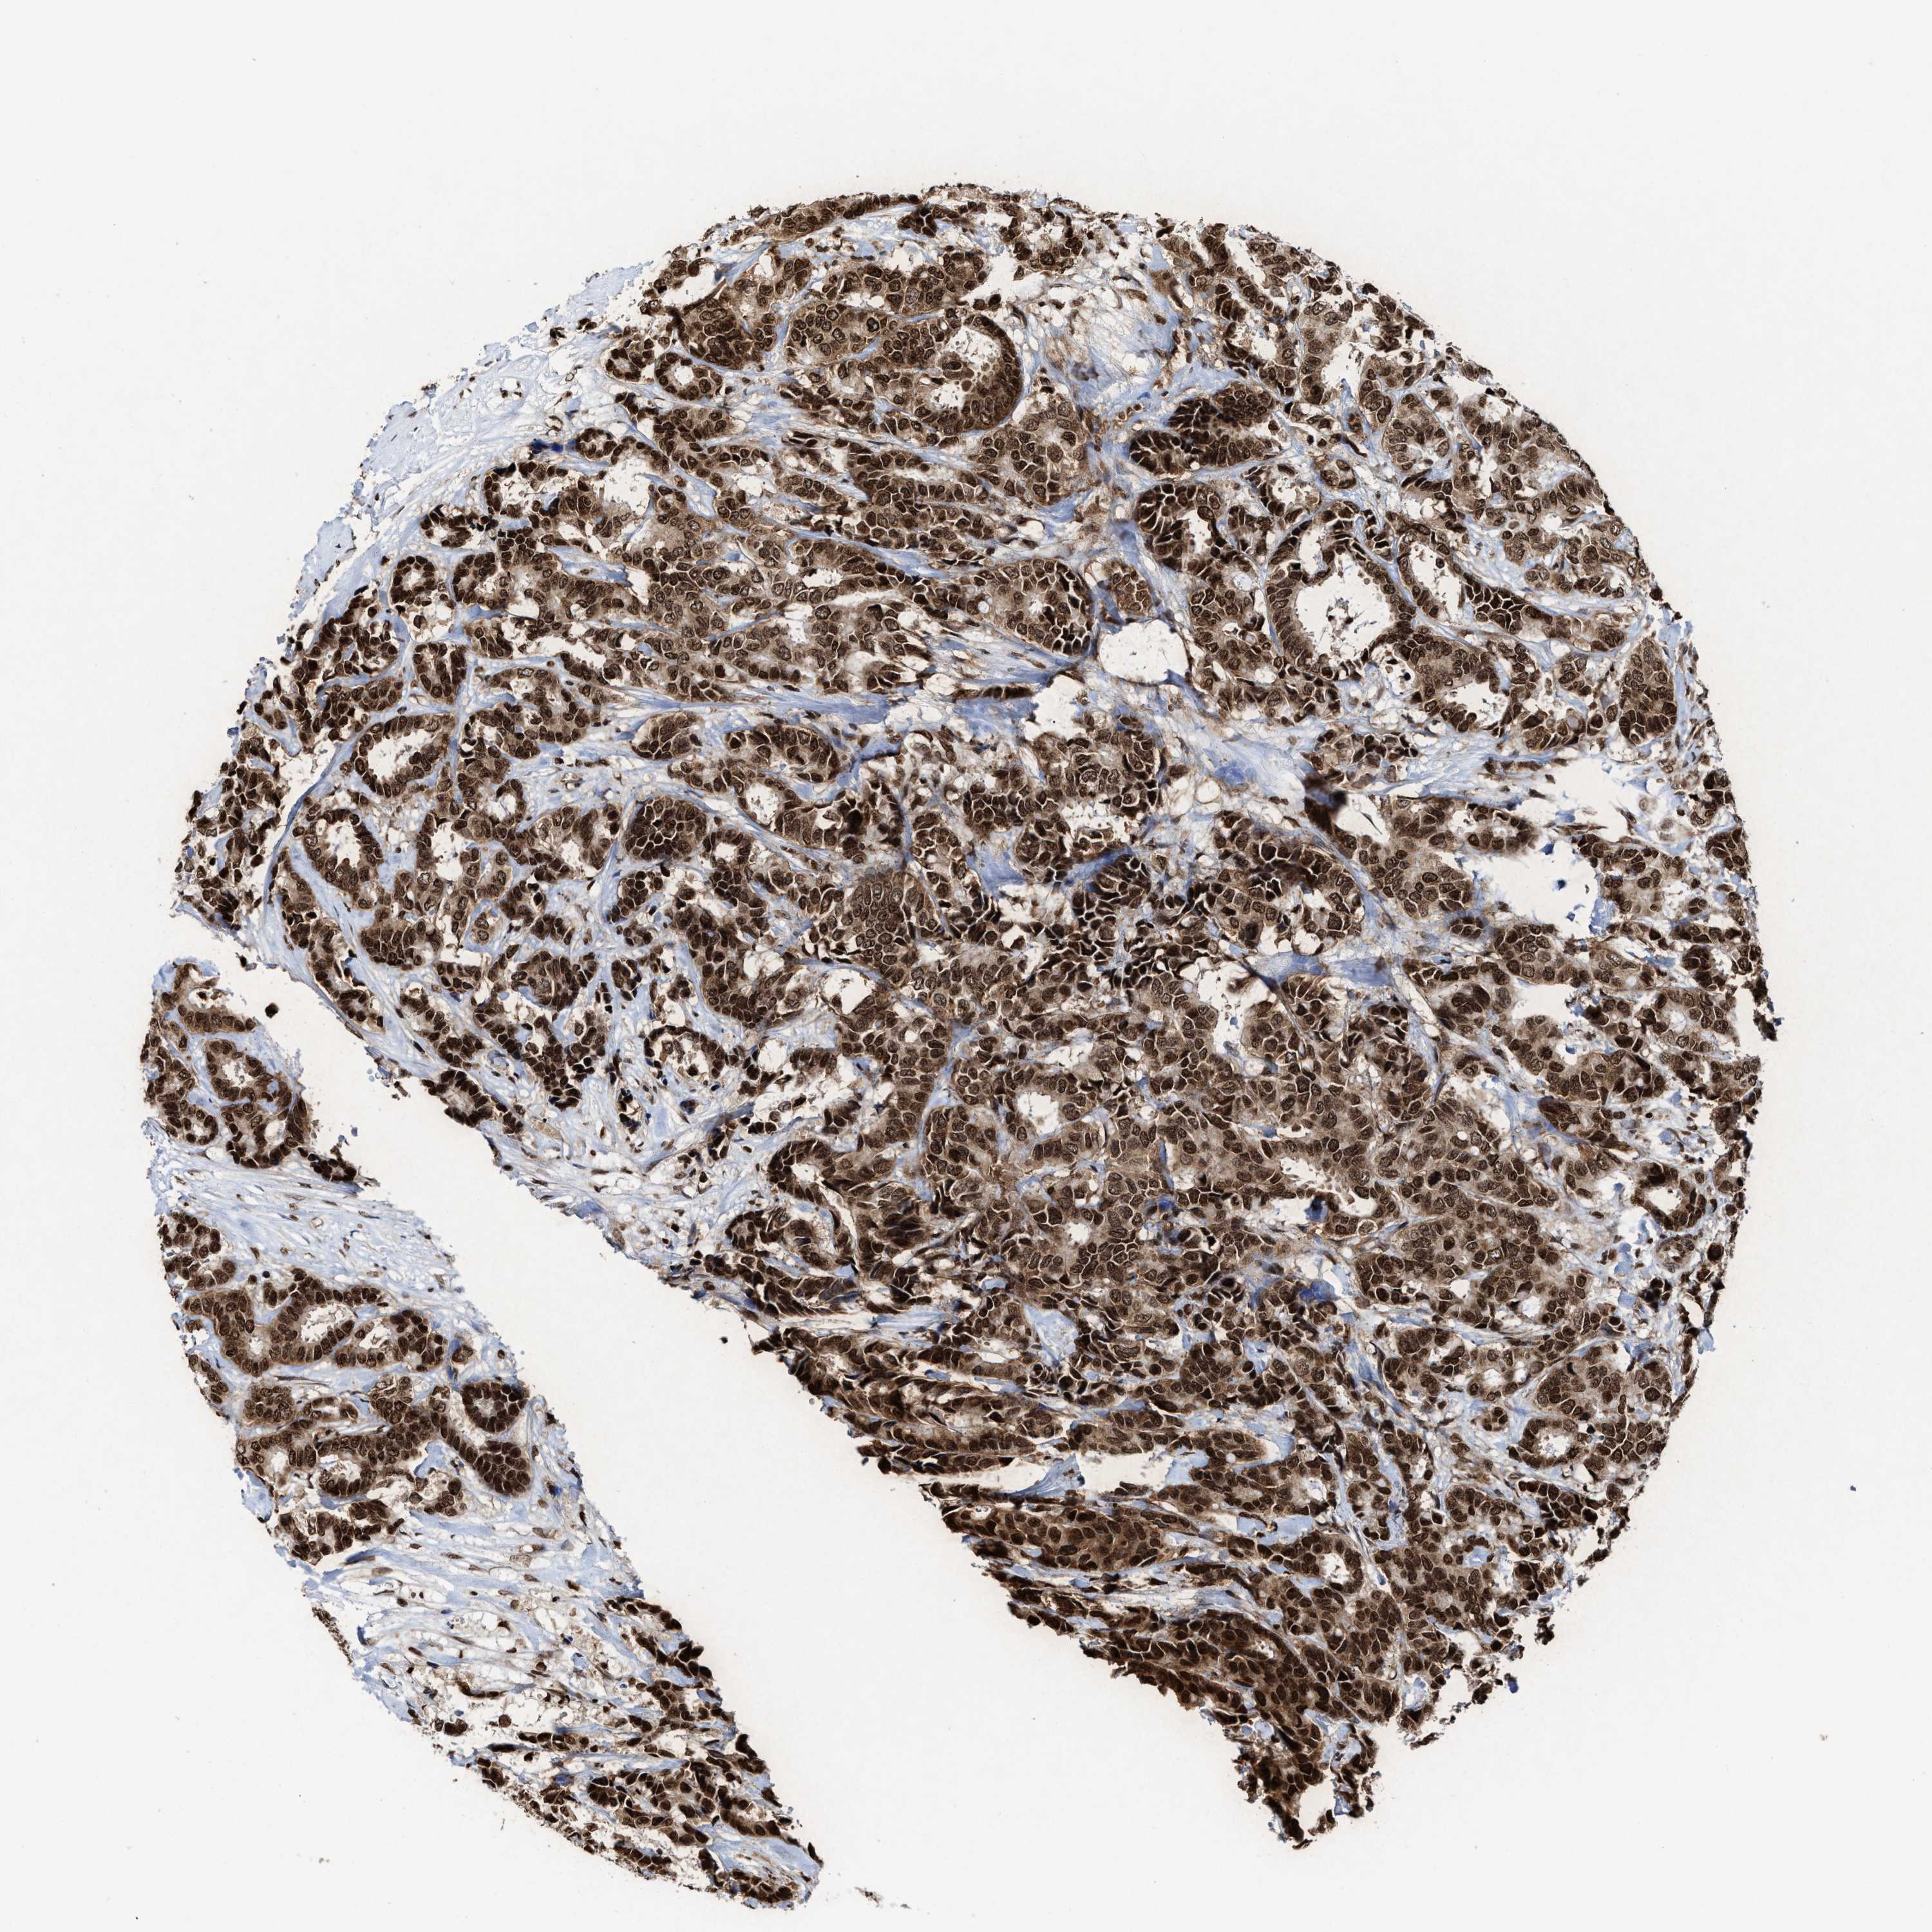

CANCER BREAST CANCER Show tissue menu

BRCA TCGA BRCA VALIDATION PROTEIN EXPRESSION